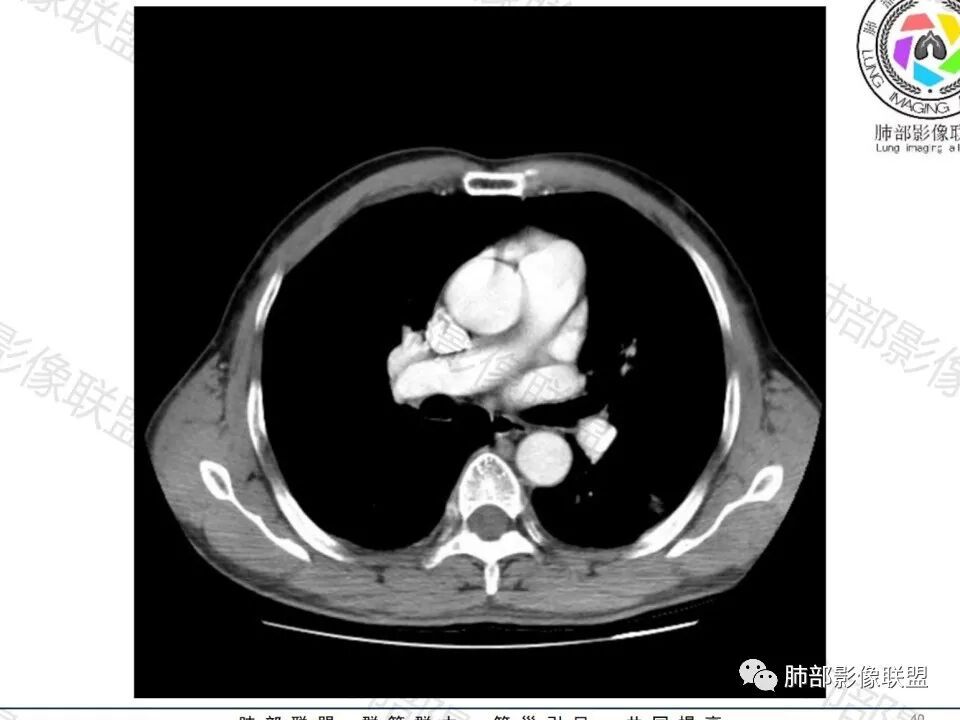

病史:男,60岁,体检左下肺结节,肿标阴性;

影像:轻微肺气肿,可能抽烟;旁边有个卫星灶4-5个,厚层无血管弯,薄层叶间裂轻度增厚,有囊腔,内侧有一个微血管,弯,另有两个微血管直,膨隆,增强血管不弯,糊墙,好像边界有些模糊,17-47-47,冠位轻度叶间裂弯。

诊断:警惕良性,隐球菌感染?

鉴别:腺癌,无磨玻璃,模糊?糊墙;纵膈窗太光滑,胸膜面广;不膨隆。支持点,薄层毛刺,强化。

类圆形,边缘稍平直,周围晕中细微毛刺,密度均匀,均匀强化,血管走形自然,稍牵拉扭曲,支气管在近端堵塞

这枚结节的纵隔窗在没有调节窗位的情况下,已经很密实了,说明这个结节里面是软组织的成分,这与普通炎性结节(隐球菌等)的密度还是有区别的,很多年前就有人提出,纵隔窗显示越大,恶性可能越大;

结节周围有磨玻璃影,边界似清不清的,但是总体不如炎性晕征那么模糊;

增强的程度很难讲,但是不均匀强化是可以确定的;

有收缩力,但是很轻,按照常理,实性结节因为有占位效应,不太会有收缩力,但是叶间胸膜有凹陷。所以讲,这个结节还是开了放心。